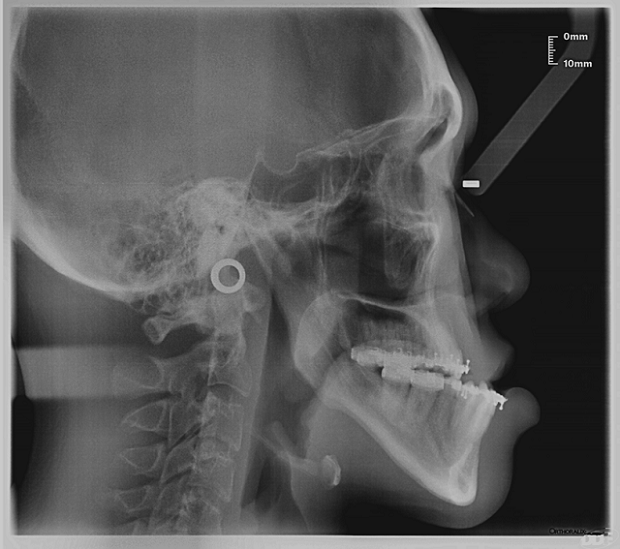

Orthognathic surgery, also known as corrective jaw surgery, aims to correct deformities or misalignment of the upper and lower jaws. These deformities and misalignments can result in malocclusions, which refer to conditions where the upper and lower teeth are misaligned when the mouth is closed — common forms include underbites, overbites or open bites.

Rather than a single procedure, orthognathic surgery is a comprehensive course of treatments combining both orthodontic and surgical approaches that can take years to complete. As orthognathic surgery is a major intervention, it is usually prescribed when patients experience difficulties in functional issues, such as chewing, biting or speaking properly.

After the teeth are positioned properly, orthognathic surgery is carried out to correct the alignment of the jawbones. During the procedure, a surgeon will make cuts to the jawbones and reposition them. After surgery, patients must continue orthodontic treatment for approximately six months to sustain the improved and final alignment of the teeth. In older patients — such as patients with OSA, who are usually diagnosed at a later stage of life — orthodontic treatment may take longer.